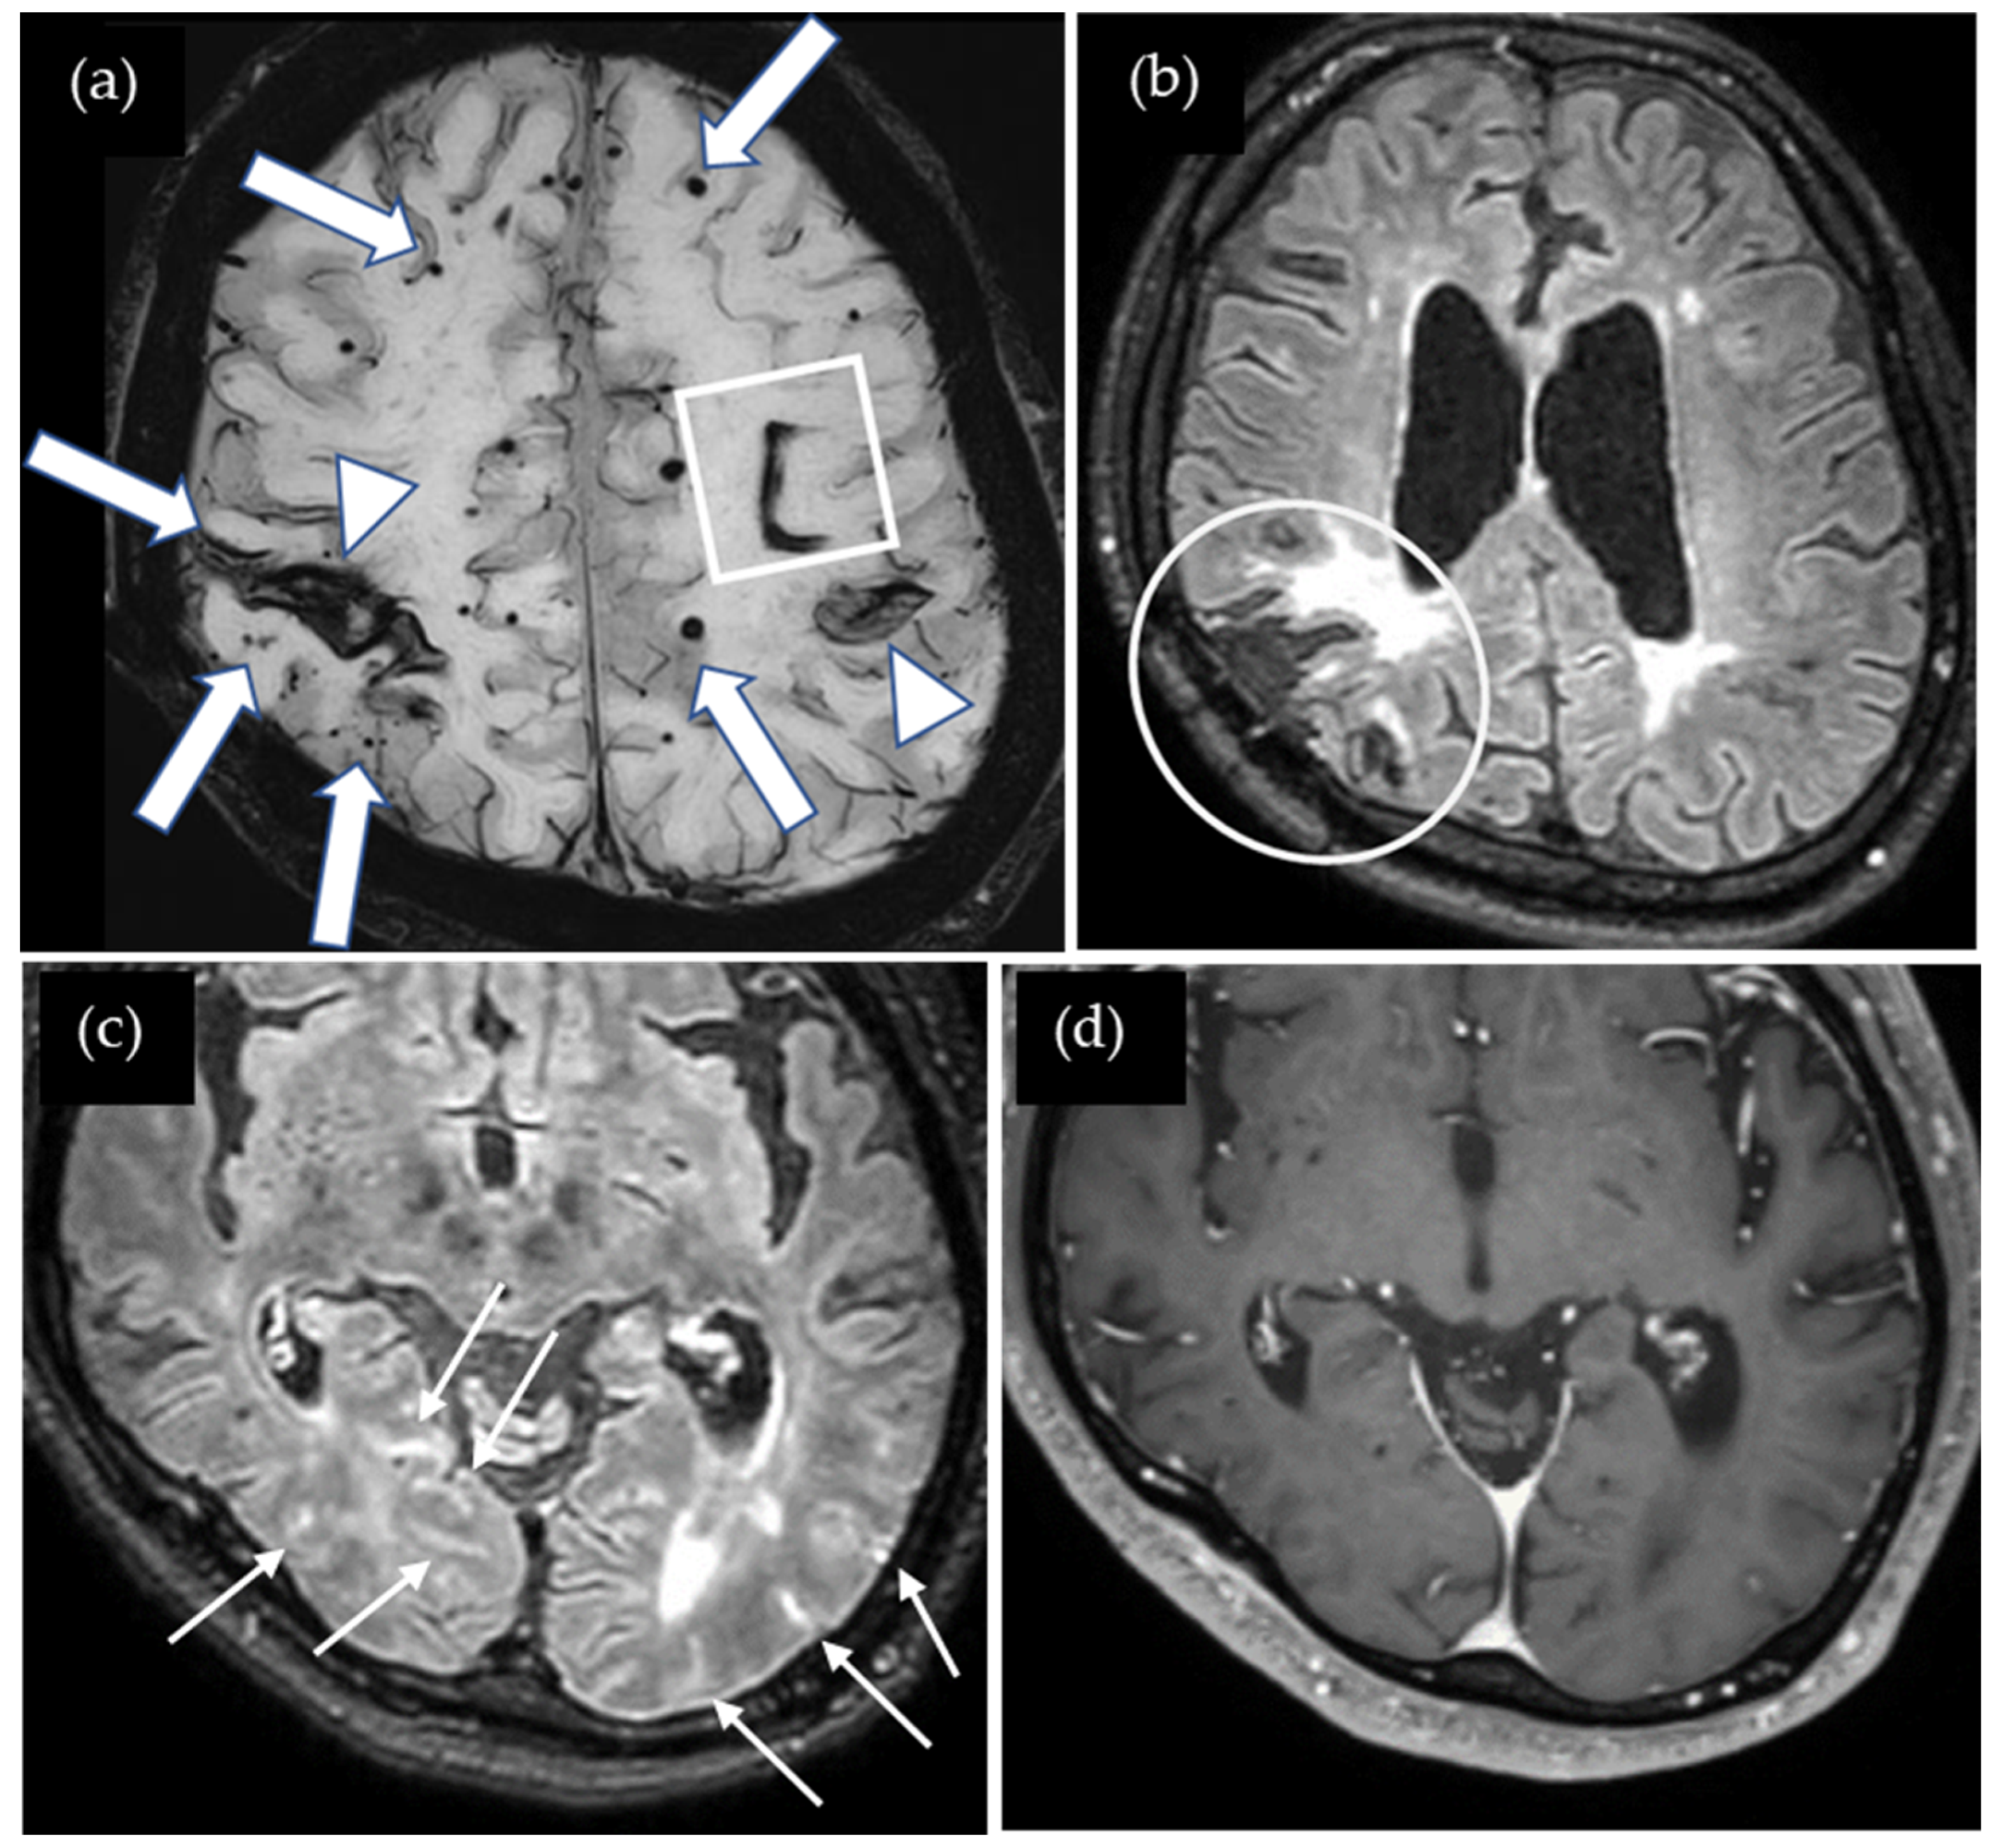

A 47-year-old woman presented with severe cognitive impairment, including episodes of not knowing where her house was, indicative of loss of orientation. Her Mini-Mental State Examination score was 14 out of 30. She underwent surgery for cerebellar medulloblastoma at age five, followed by whole-brain radiation therapy and shunting for obstructive hydrocephalus. Cadaveric dura mater use was not confirmed. She had no history of hypertension or familial CAA. Susceptibility-weighted imaging (SWI) showed multiple cSS in both cerebral hemispheres as well as multiple CMBs located mainly in the cortex, and several microbleeds were detected in the cerebellum (Figure 1). The CAA- SVD score was 5 based on the previous literature [5], consisting of two points for lobar CMBs, two points for cSS, zero points for CSO-PVSs, and one point for WMH. Contrast-enhanced 3D FLAIR showed sulcal enhancement extending from the temporal to occipital lobes bilaterally while enhancement was not detected on the contrast-enhanced 3D gradient echo (GRE) T1-weighted image. Additionally, the T1-weighted image shows global brain atrophy. Neither cerebrospinal fluid (CSF) examination nor amyloid positron emission tomography (PET) was performed. Thus, this case was considered a possible iCAA based on the criteria [1].

Figure 1.

(a) SWI shows numerous lobar cerebral microbleeds (CMBs) (arrows) and cortical superficial siderosis (cSS) (arrow heads); (b) non-contrast 3D FLAIR shows postoperative changes in the cerebellum (circle); (c) contrast-enhanced 3D FLAIR shows sulcal enhancement in the bilateral occipital lobes (small arrows) while enhancement was not detected on (d) the contrast-enhanced 3D gradient echo (GRE) T1-weighted image.